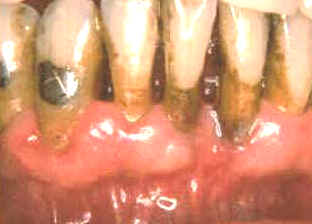

La imagen muestra

la condición 3 semanas después del tratamiento. La curación ha

progresado pero algo más de placa puede observarse en comparación al

fotograma anterior. El paciente ha reducido el control químico de placa

bacteriana por el sabor

amargo del cclorhexidine. Para

conservar a menudo el resultado del tratamiento es necesario que el

paciente realice el control químico de la placa bacteriana a intervalos

regulares y debe mantener un correcto cepillado dental. El éxito del

tratamiento depende fundamentalmente de la colaboración del paciente en

su hábito higiénico. |